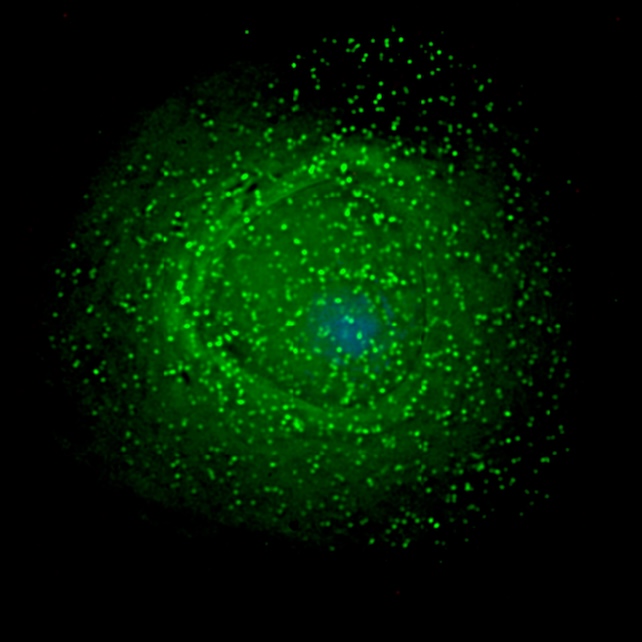

In its latent stage, HIV can persist in certain host cells as a dormant "provirus" – a viral genome that inserts itself into a host cell's DNA.

The immune system's T helper cells are the main latent reservoir, but not the only one. HIV also hides in skin cells, white blood cells, and organ-specific cells such as podocytes from the kidneys and support cells for neurons.

According to the new study, HIV achieves this with a tissue-specific approach, cloaking itself in a host cell's DNA by adjusting its behavior to fit the setting. In the brain, for example, it avoids genes and hides in less active regions of DNA.

The authors analyzed how often HIV integrated itself into specific parts of the host genome, then compared the patterns they observed across different body tissues from different people.